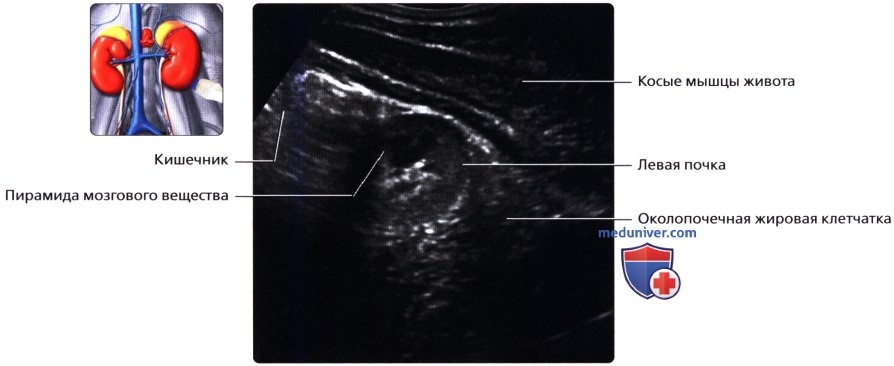

а) Анатомия почек:

2. Топографическая анатомия почки:

• Лежат в забрюшинном пространстве, окружены почечной фасцией (фасция Героты)

• У взрослого каждая почка около 9-14 см в длину и 5 см в ширину

• Обе почки лежат «на» квадратных мышцах поясницы, латеральнее поясничных мышц

б) Лучевая анатомия почки:

1. Обзор:

• Забрюшинные структуры бобовидной формы с четким контуром, смещающиеся при дыхании

в) Особенности визуализации почек:

1. Рекомендации по визуализации:

• Правая почка:

о Печень используется в качестве акустического окна

о Датчик устанавливается в подреберье или в межреберный промежуток

о Выполняйте исследование при различной глубине вдохе

о Попросите пациента немного повернуться влево, приподняв правый бок и выполняйте сканирование с боковой/заднебоковой поверхности

• Левая почка:

о Ее труднее визуализировать из-за газа в тонкой кишке и в селезеночном изгибе ободочной кишки

о Обычно левую почку проще визуализировать, используя заднебоковой эхографический доступ и попросив пациента немного повернуться вправо приподняв левый бок

о В сложных случаях полностью переверните пациента в положение лежа на правом боку, подложите подушку под его правый бок и попросите его поднять левую руку над головой:

— Для исследования верхнего полюса левой почки можно использовать селезенку как акустическое окно

о Задний эхографический доступ:

— Удобен при инвазивных процедурах (биопсия почки, нефростомия)

— Качество изображения может снижаться из-за теней от околопозвоночных мышц и ребер